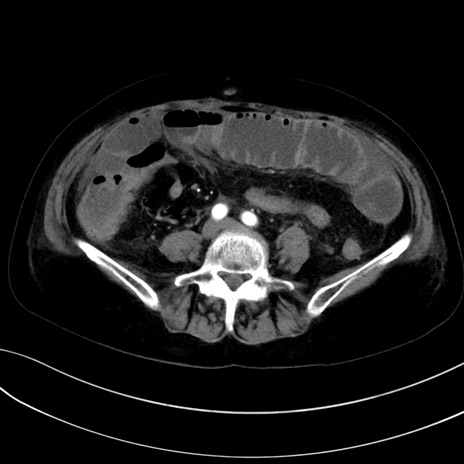

症例13 CT(横断像)1日半後